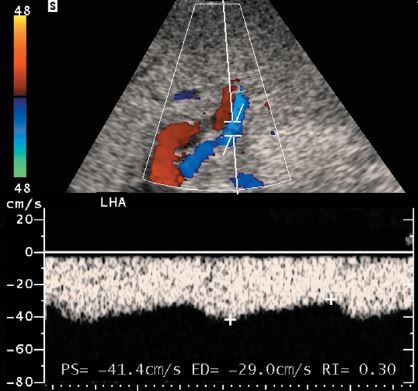

HA thrombosis following liver transplant

• Significant hepatic artery stenosis and hepatic artery thrombosis with collateral flow can be detected with Doppler scanning by noting a blunted arterial waveform distal to the stenosis. Blunting can be quantified in several ways.

• The easiest is by measuring the resistive index. If the resistive index is less than 0.4, the waveform should be considered severely blunted, and a diagnosis of hepatic artery stenosis or thrombosis should be made.

• In this case, the left hepatic artery serves as a collateral receiving blood from the left gastric artery

• Since the bile ducts are dependent on hepatic arterial supply, arterial thrombosis causes biliary ischemia and can produce strictures or complete necrosis of the ducts.